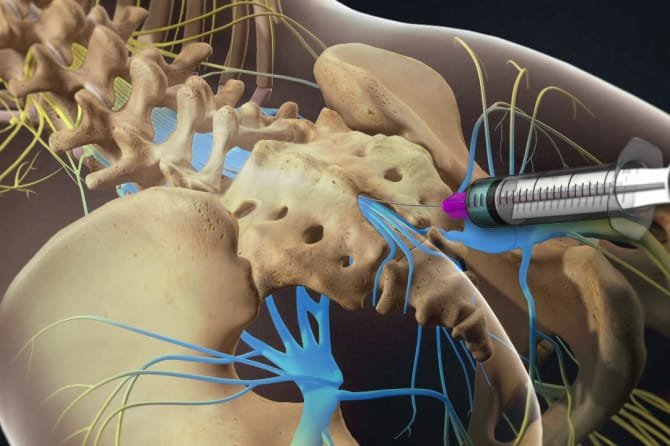

A caudal epidural injection involves delivering a mixture of anti-inflammatory steroids and local anesthetic into the epidural space at the base of the spine (the sacral hiatus). This treatment reduces inflammation and blocks pain signals, offering relief from a range of conditions affecting the lower back and legs.

Procedure: What Does a Caudal Epidural Injection Involve?

Preparation

Before the procedure, you’ll be asked to lie face down on a treatment table. The injection site near the tailbone is cleansed, and a local anesthetic is applied to minimize discomfort.

Injection Mixture

The injection contains a mixture of:

- Corticosteroids: To reduce inflammation and swelling in the affected area.

- Local anesthetic: To numb the area and provide immediate pain relief.

Image Guidance

To ensure precision and safety, the injection is administered under image guidance, which may be:

- Fluoroscopy (X-ray): Provides real-time imaging and is the most commonly used guidance method. A contrast dye is injected to confirm the correct placement of the needle.

Technique

Sterilization and Anesthesia: The area is cleaned with an antiseptic solution, and a local anesthetic is applied to numb the skin and surrounding tissue.

Needle Insertion: A needle is carefully inserted into the caudal epidural space using fluoroscopic or ultrasound guidance.

Injection: Once the correct position is confirmed, the steroid-anesthetic mixture is slowly injected into the epidural space. The entire process takes around 15 to 30 minutes.